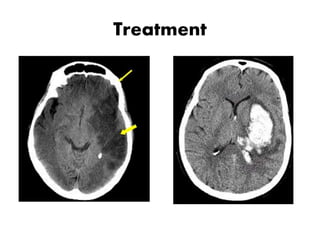

– CT scan of head ( To know whether the lesion is

vascular origin or ICSOL or anything else ;if

vascular whether it is ischemic or hemorrhagic ) :

If comes within 24 hours of onset

– MRI of brain : If comes after 7 days